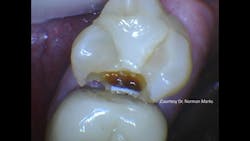

Figure 2: Obviously, the radiograph in Figure 1 did not show the major carious lesion.

Recently, one of our practicing dentist team members who donates significant time to Clinicians Report Foundation and Practical Clinical Courses sent me a clinical example that frustrated both of us (figures 1 and 2). As you observe Figure 1, you will immediately see a lesion on the mandibular second molar and—perhaps—a small lesion on the maxillary first premolar. But do you see the lesion on the maxillary second molar? As you observe Figure 2, you are shocked to see the depth of the MO lesion that was not visible on the radiograph.

In my experience over the past several years, I admit that I miss many lesions that finally show up at subsequent appointments as larger lesions with the problems already described.